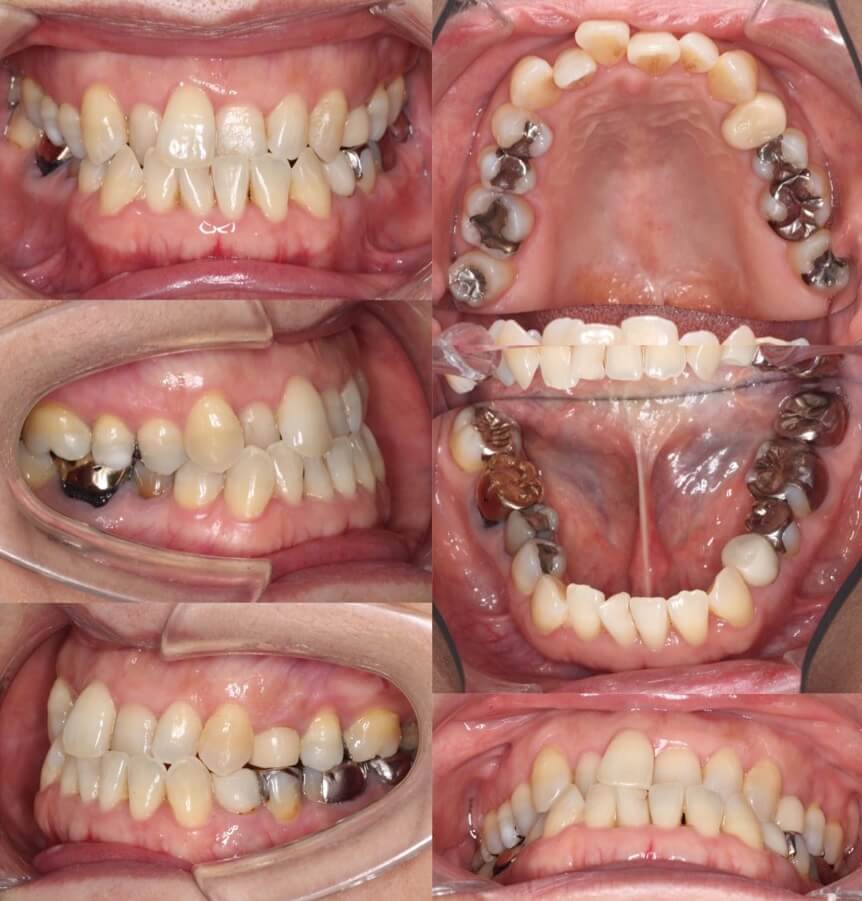

43歳女性・唇側矯正装置・抜歯

<症例概要>

主訴:前歯のがたつきと・かみ合わせ

年齢・性別:43歳女性

住まい:千葉県佐倉い市

症状:叢生・前歯交叉咬合・左上5番萌出不全

治療方針:右上下4番・左上下5番(計4本)

治療装置:唇側矯正装置

固定装置:リンガルアーチ

治療期間:2年6か月

リテーナー:下フィックス+上下クリアタイプ

治療費用:968,000(税込)

代表的副作用:痛み・治療後の後戻り・歯根吸収・歯髄壊死・歯肉退縮

▶︎その他の副作用

抜歯矯正ではふつう4番を抜歯するのですが、歯の状況によっては5番を抜歯することもあります。左上の5番の歯が半分弱しか出てきてないことと、左下の5番が大きく外側に転位していることから、左側のみ5番を抜歯し矯正治療を行いました。やや歯列の正中線は、4番を抜歯した右側に引っ張られたのですが、患者さんはそこまで気にしていませんでした。